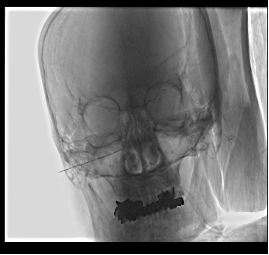

蝶腭神经节刺激